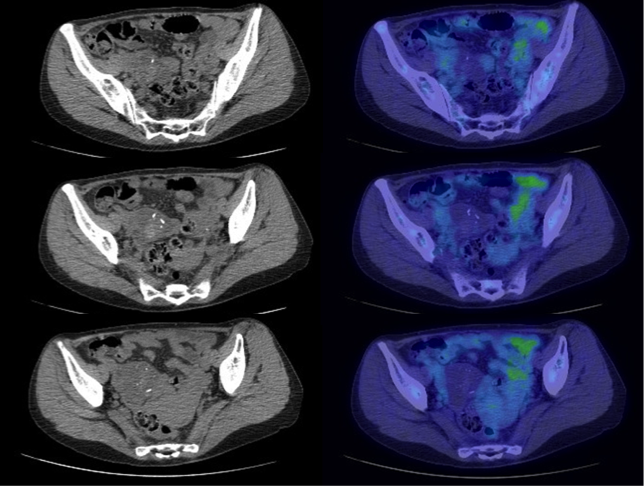

A 56 year old housewife, who was a non-smoker and non-drinker, presented with dry cough for three months. She denied other complaint and she enjoyed a good past health. Her physical examination was unremarkable. Her chest X-ray (CXR) showed patchy infiltrates in bilateral lower zones and several lung nodules bilaterally (Fig 1). Her initial blood tests including complete blood picture, renal & liver function test, erythrocyte sedimentation rate, urate, lactate dehydrogenase and tumor markers (including carcinoembryonic antigen, alpha-fetoprotein, CA 15.3, CA 19.9 and CA 125) were normal. Her sputum was negative for culture, acid fast bacilli and cytology. Her urine routine microscopy was also normal. Contrast computer tomography (CT) thorax showed bilateral lung nodules with size 0.5-2cm, bilateral thin walled lung cysts with size 0.5-2.5cm and sub-segmental collapse of right middle lobe. Some of the nodules had speckles of calcifications inside (Fig 2A, 2B). Fibre-optic bronchoscopy and transbronchial biopsy (FOB+TBBx) were not diagnostic. We had discussed with her about different investigation options included positron emission tomography (PET)-CT and repeating biopsy by FOB+TBBx under fluoroscopy guidance or CT guided fine needle aspiration (FNA). She opted for PET-CT. Her PET-CT was reported as “There were multiple hyper-metabolic nodules (maximum standardized uptake value (SUVmax ) 4.4). They were suspicious of metastases.” There were also multiple hypo-metabolic lucent cystic lesions scattered on both lungs. A complex cystic mass with calcification and some F-18 fluorodeoxyglucose (FDG) avidity was found incidentally at the right adnexal region (Fig 3A, 3B). At that juncture, the working diagnosis was gynaecological malignancy with multiple lung metastases. FOB+TBBx repeated under fluoroscopy guidance showed nodular deposition of extracellular amorphous eosinophilic material in the alveolar spaces. These depositions were salmon pink in Congo red section, and they showed yellow-green birefringence in polarized microscopy. The histological feature was compatible with amyloid. Total abdominal hysterectomy and bilateral salpingo-oophorectomy was done by the gynaecologist and the right adnexal lesion was found to be a mature ovarian teratoma with thyroid tissue. Thus the right ovarian teratoma was just an incidental finding and was not related to the amyloidosis. Further assessment and workup were done to look for possible condition that was known to be associated with amyloidosis such as chronic inflammatory diseases and monoclonal plasma cell dyscrasias. Further enquiry revealed she had chronic dry mouth for over 10 years. Her antinuclear antibody (ANA) titer was raised (1/640) and her anti-Ro (SS-A) titer was positive. Her schirmer test was 0mm over both eyes, indicating severe dry eye. Although the histology of her salivary gland biopsy was reported as within normal limit, she was considered as a case of primary Sjogren’s syndrome by the rheumatologist and symptomatic treatment was provided. Clinically, no other organ was involved by the amyloidosis. Thus the final diagnosis was nodulocystic pulmonary amyloidosis associated with primary Sjogren’s syndrome. An interval CT thorax about two years later showed no significant interval change.

Figure 3a and 3b